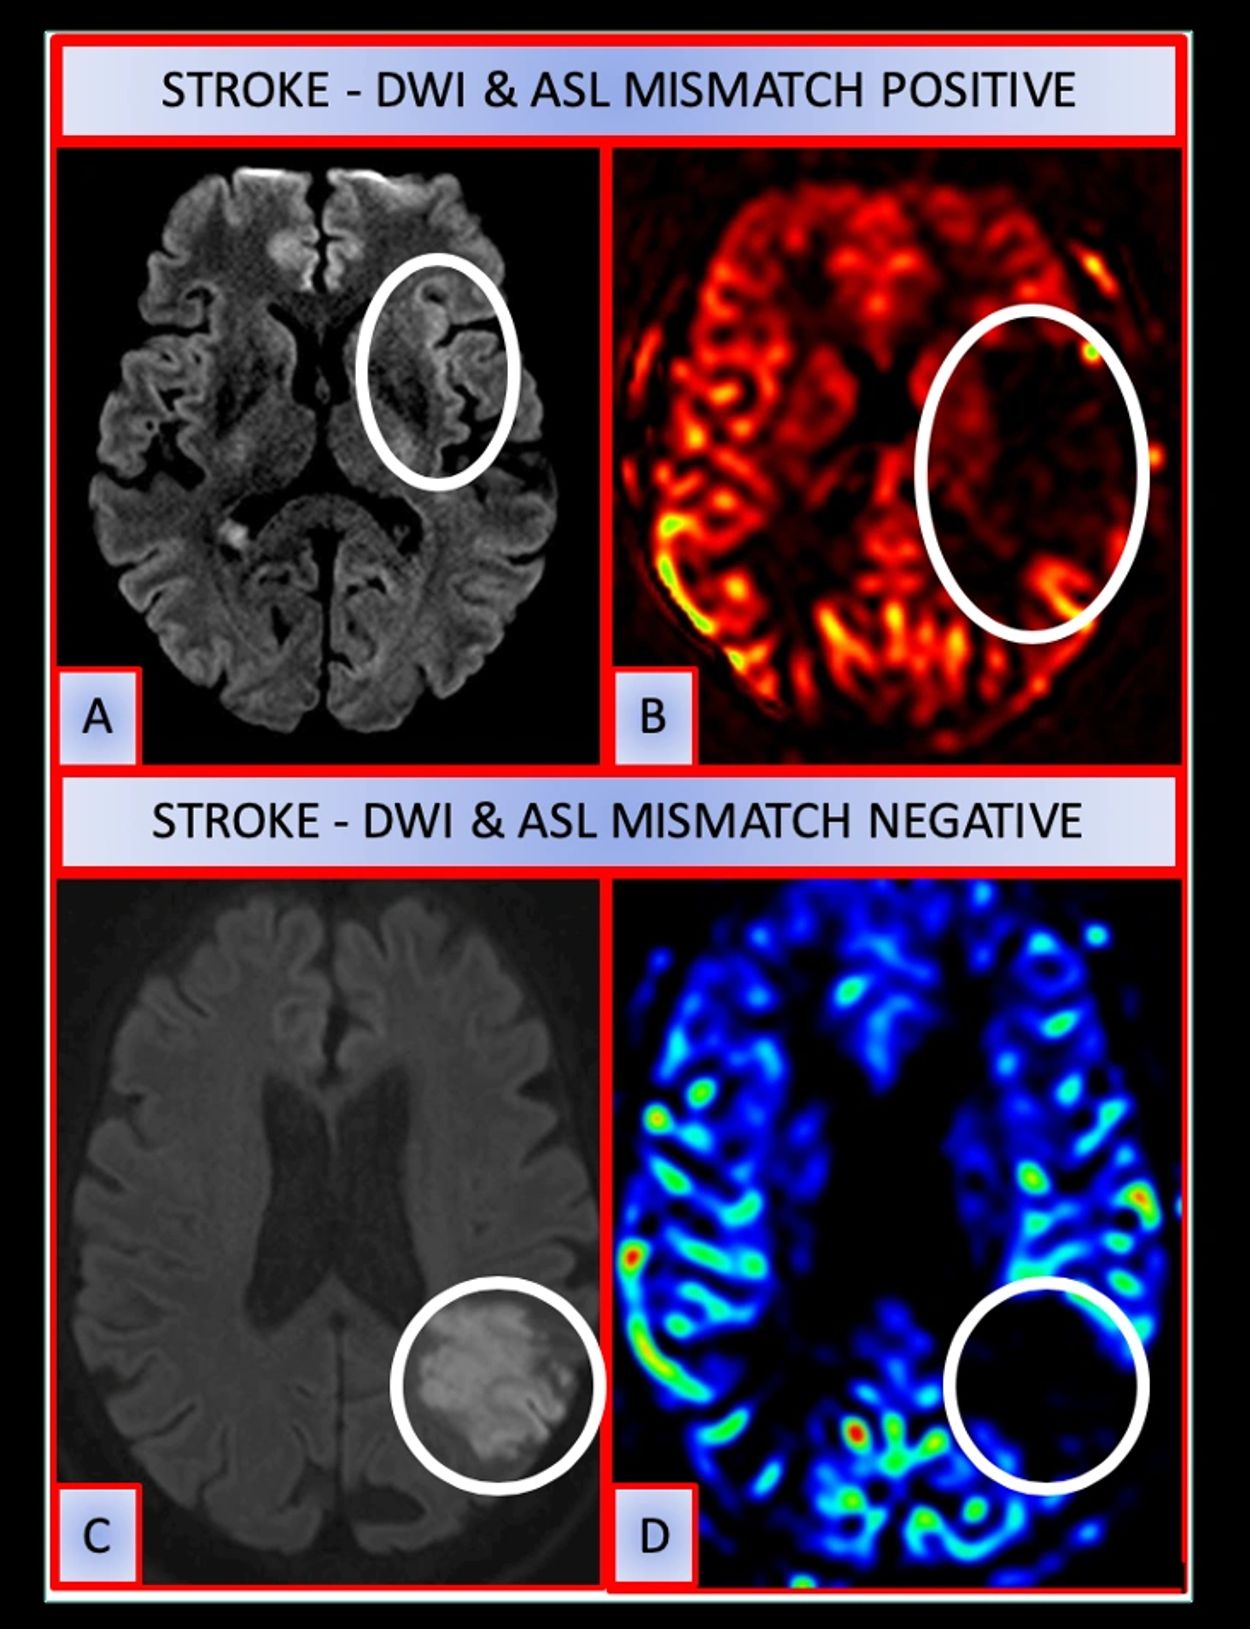

Arterial spin labelling (ASL) is a noncontrast, magnetic resonance perfusion technique which can provide information about the parenchymal perfusion status and collaterals in acute stroke. Its role in the setting of large vessel occlusion (LVO) is underutilized due to the limited availability of magnetic resonance imaging (MRI) in the emergency settings. However, it might serve as an useful adjunct to other perfusion modalities in future. Objective To study ASL perfusion patterns in anterior circulation LVO stroke and evaluate the presence of arterial transit artefacts (ATA) as a surrogate marker of collaterals.

We performed a retrospective analysis of our mechanical thrombectomy database over the last 2 years for acute stroke cases in which ASL perfusion as part of MRI was performed. ASL perfusion patterns in acute LVO stroke were reviewed, with respect to presence of ATA and diffusion-weighted imaging (DWI)-ASL mismatch. Inter-rater reliability was analyzed between 2 readers of varying experience. Baseline variables were analyzed between those with and without ATA.

Out of 95 patients, 78 had anterior circulation occlusions, among which 27 had ASL. Type I (with ATAs) was seen in 11 patients and all of these had DWI mismatch. Type II (without ATAs) was seen in 16 patients. Of these, 15 had mismatch with DWI and only 1 had no mismatch. Inter-rater reliability for the detection of ATA on ASL was substantial (Cohen’s k—0.64). No statistical significance was noted between ATA and clinical outcomes.

ASL patterns vary amongst patients with LVO stroke and can be classified based on the presence of ATA since resulting DWI mismatch actually indicates a pseudo-perfusion deficit.